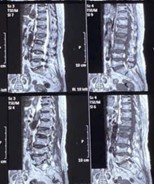

TÓM TẮT Gãy đốt sống mới sau bơm xi măng điều trị xẹp đốt sống do loãng xương là biến chứng đã được mô tả trong nhiều nghiên cứu, đặc biệt tại các đốt sống liền kề hoặc ở các đốt sống khác và có thể xuất hiện rất sớm. Chúng tôi báo cáo một